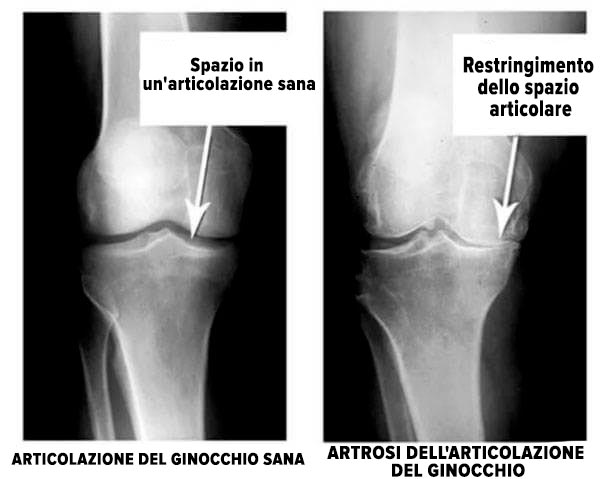

Guarda queste immagini, puoi vedere che nell'immagine a destra manca lo spazio articolare, le ossa si sfregano tra loro e causano un dolore intenso. E questo processo è molto difficile da fermare! Dopo un paio d'anni, una persona sarà disabile e non sarà in grado di prendersi cura di se stessa.